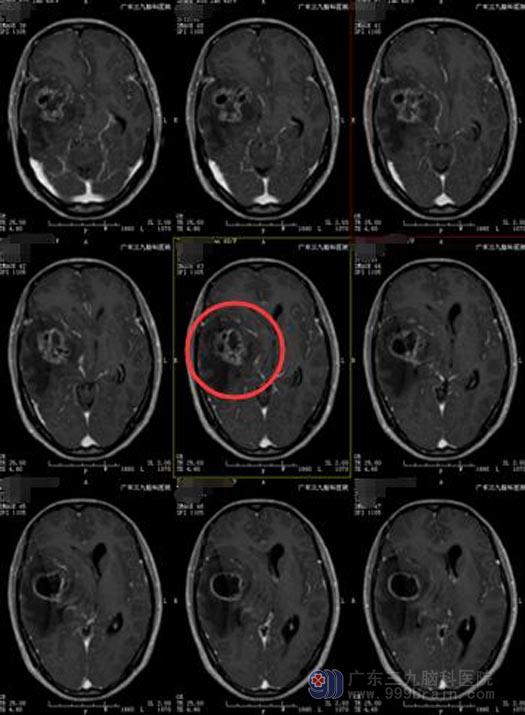

在广东三九脑科医院综合神经外科,急诊行CT及MR头颅影像学检查,确诊为神经胶质瘤,右侧颞岛叶占位伴卒中,病变内示多发囊状影,增强后呈明显花环状异常强化影,范围约为5.3cm×5.2cm×5.3cm。

由于肿瘤较大,位置邻近基底节区,右侧颞叶底部有少许出血,且有右侧大脑镰下疝形成,基底节区有重要的感觉和肢体运动功能所在,血供丰富,手术入路较深,胶质瘤又为恶性肿瘤,需尽可能扩大切除区域,手术难度非常大。